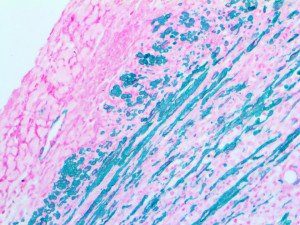

This activation induces inflammatory monocytes to highly express IL-6, starting a localized and then systemic cascade effect that results in hyperproduction of IL-6, which accelerates the inflammatory process. Because IL-6 also increases vascular permeability, excessive levels cause blood vessels to become very leaky. This, along with clotting factors released from vascular endothelial cells, stimulates the coagulation cascade, resulting in microthrombosis (tiny clots), which leads to ischemia and tissue death of the kidney, intestines, heart, liver, brain and extremities.